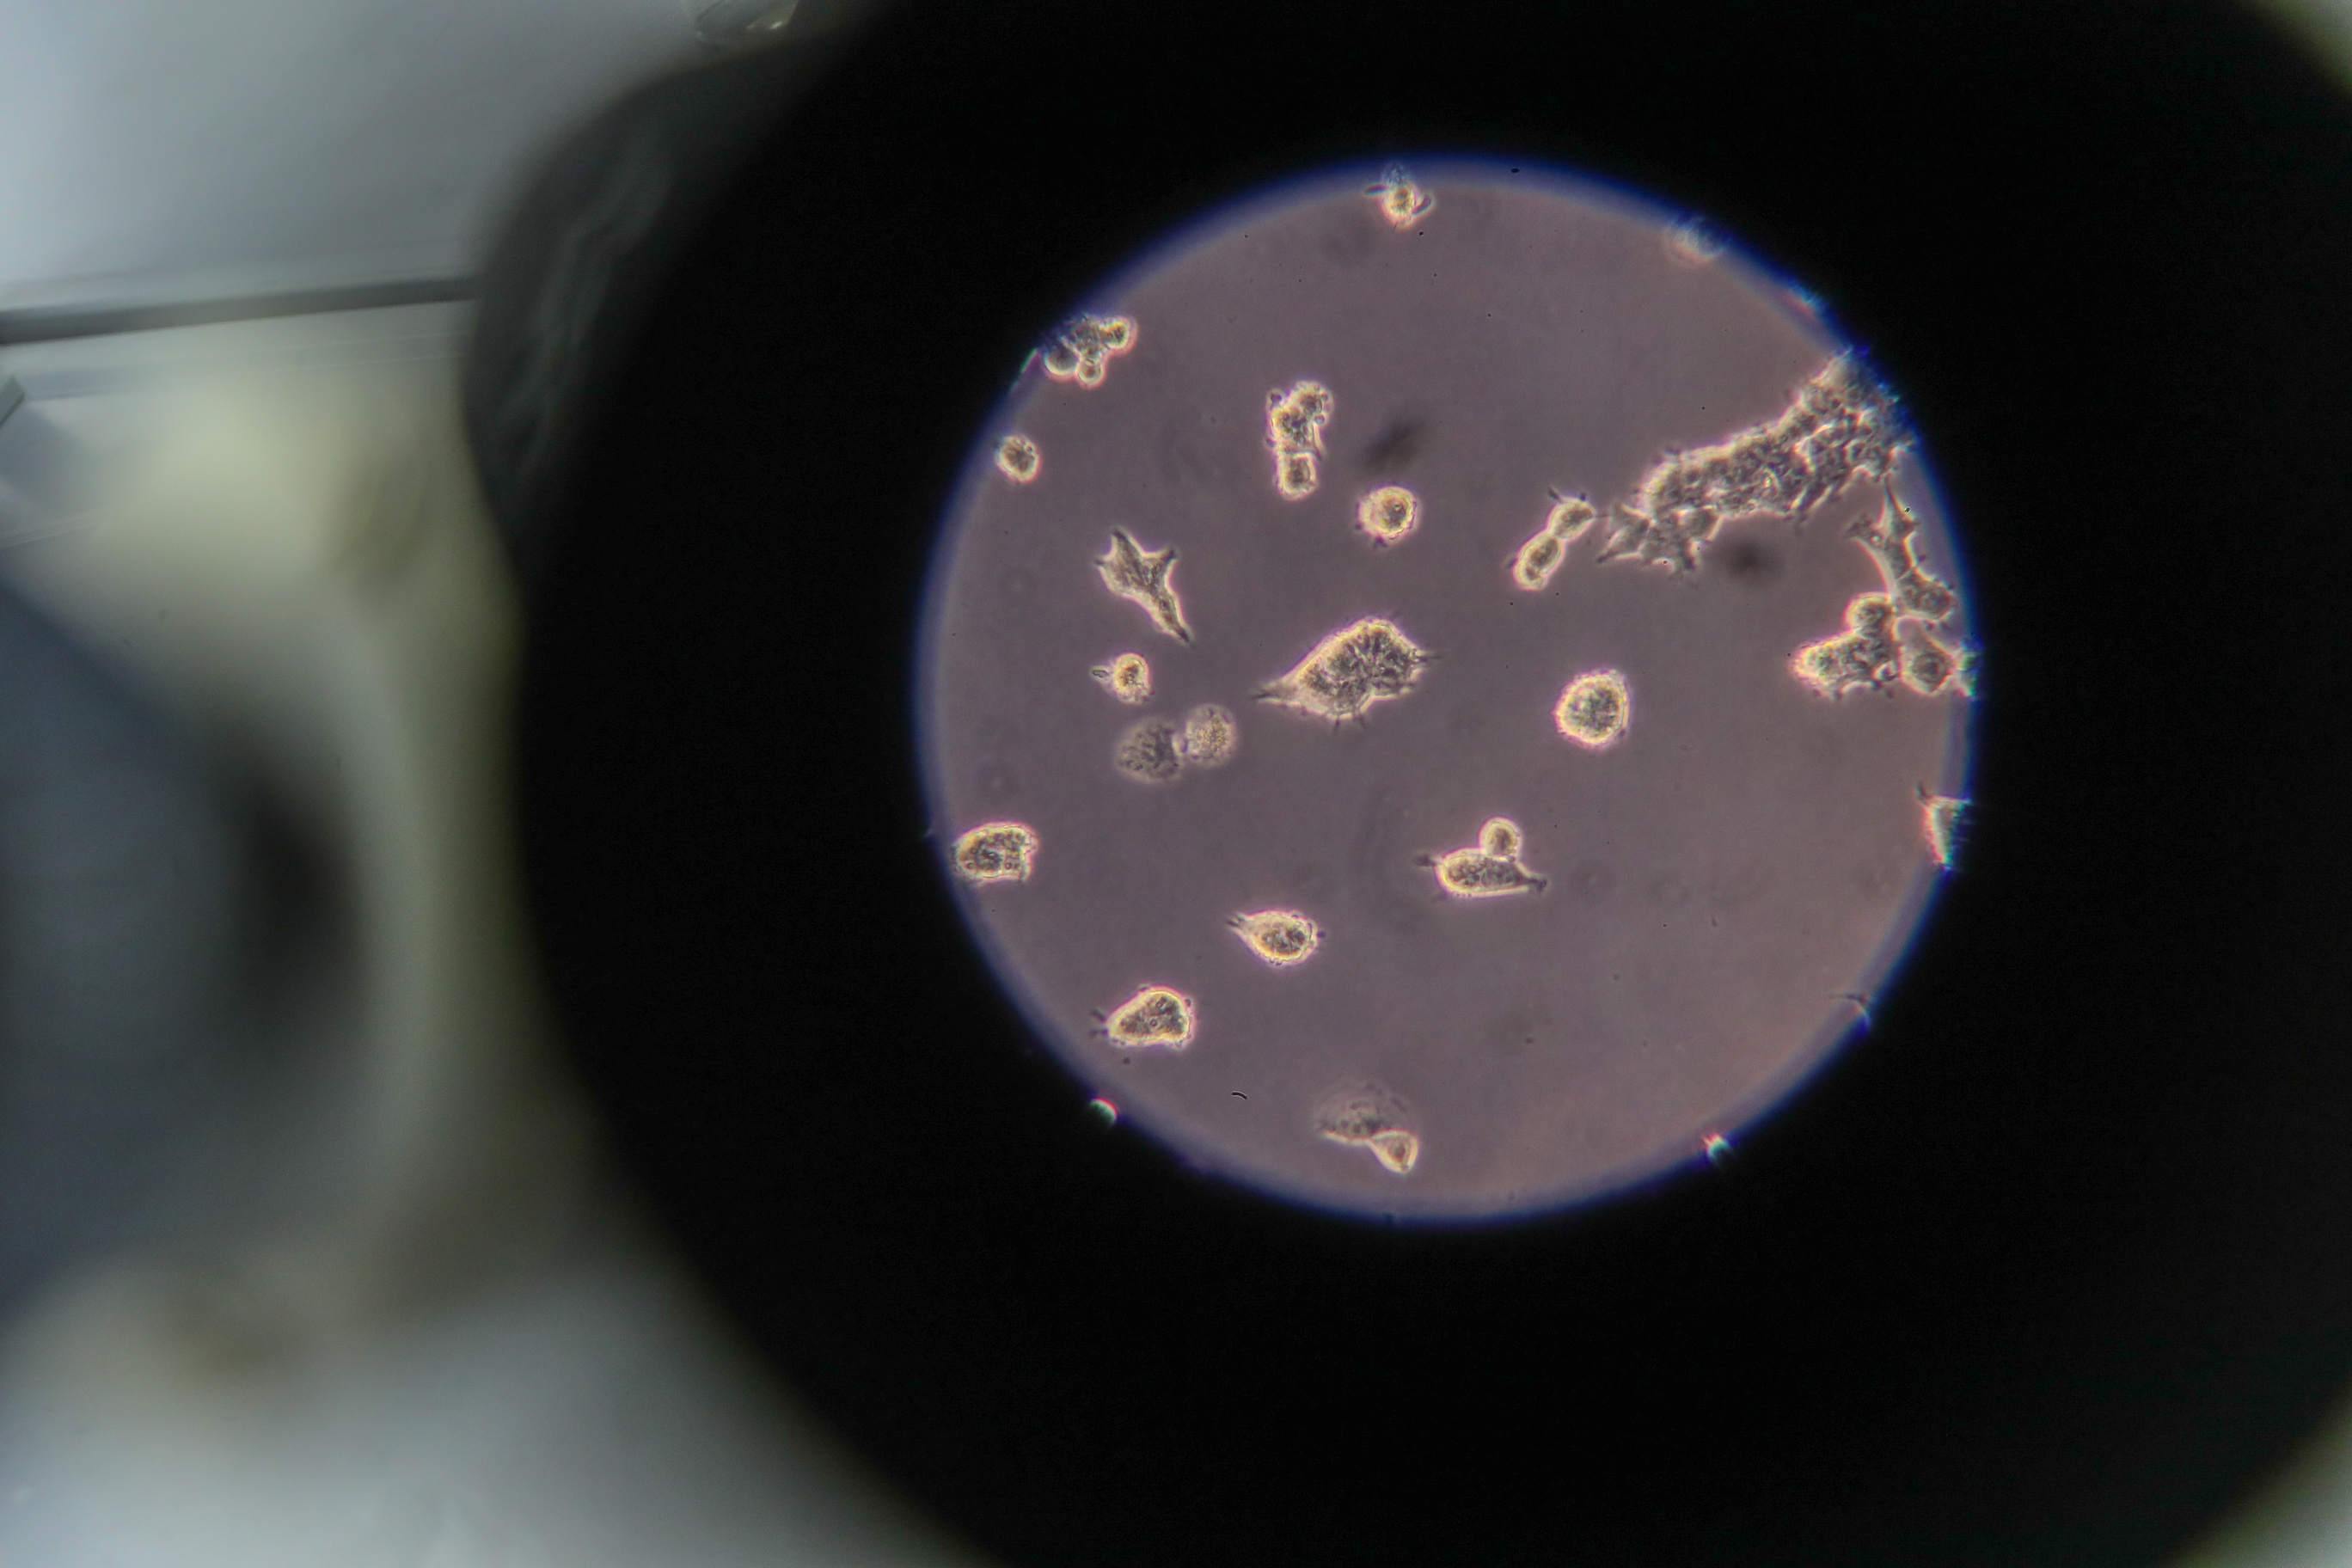

MOSCOW, December 15. /TASS/. Scientists of Russia’s Federal Medical Biological Agency (FMBA) have developed algorithms capable of forecasting with high precision the severity of a course of the coronavirus infection, the agency’s press service told TASS.